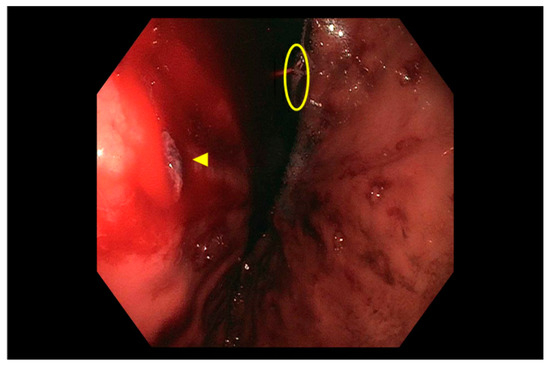

2.7. Rare Causes of UGIB

3. Small Bowel Bleeding